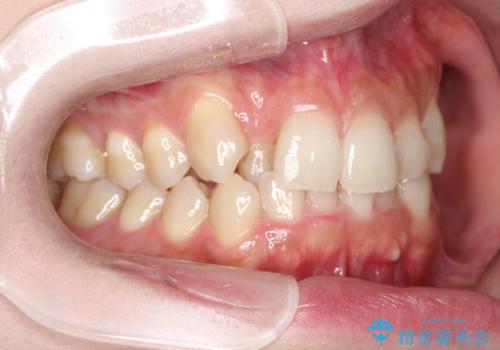

- 八重歯を治したいとのことで来院されました。

右上の犬歯が外側に飛び出して、二番目の歯が内側に入っている状態でした。

上の奥歯を後方に移動させてスペースを確保して、前歯のガタガタを改善する計画としました。